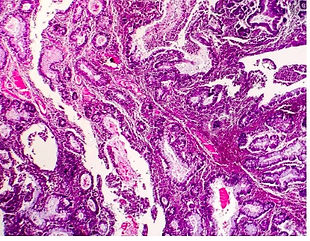

Cancer - prostate

What Is Adenocarcinoma? If your doctor tells you that you have adenocarcinoma, it means you have a type of cancer that starts in the glands that line the inside of one of your organs.Adenocarcinoma can happen in many places, like your colon, breasts, esophagus, lungs, pancreas, or prostate.It's natu

Colon Cancer